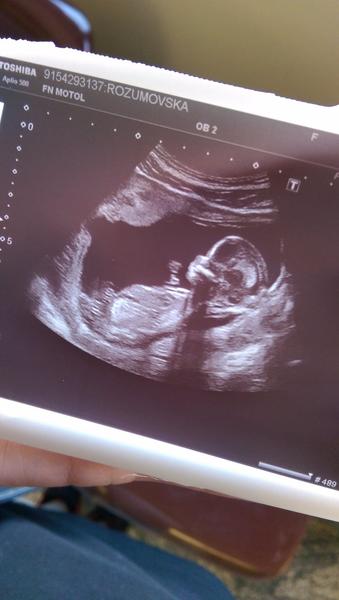

@marketka00 Gatuluju, krasne spravy!!!!!!!! To uz je velke miminecko!

@marketka00 to už je krásný prcek! Gratuluji!

@hribek bylo to hrozne fajn 🙂 miminko tak uplne krasne uvidite